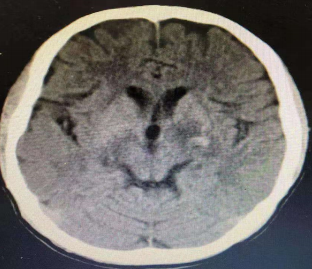

答案:生殖细胞瘤。生殖细胞瘤可发生于中线部位(松果体或鞍上区)、纵隔或骶尾区等其它部位;突出临床表现是内分泌紊乱,表现为上视障碍和性早熟,同时可伴有下丘脑功能障碍,如尿崩、烦渴、嗜睡及肥胖;生殖细胞瘤有特定发生部位和高的钙化发生率,是确诊的主要依据。患者头部CT如下: